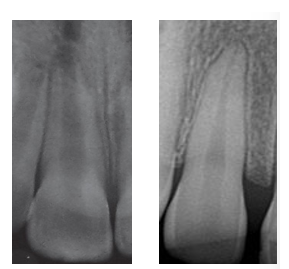

Immature vs mature teeth roots

Immature:

Shorter roots (tooth cannot withstand a lot of force, stage 1 and 2 may not be suitable for any pulp therapy)

Wide open apex (allows more blood to enter roots - better healing, also nothing stopping extrusion of material)

Thin dentine walls (affects the prognosis of tooth, trauma may fracture the tooth in the future when treating immature teeth)

Mature:

Closed apex

Long root

Thin dentine walls